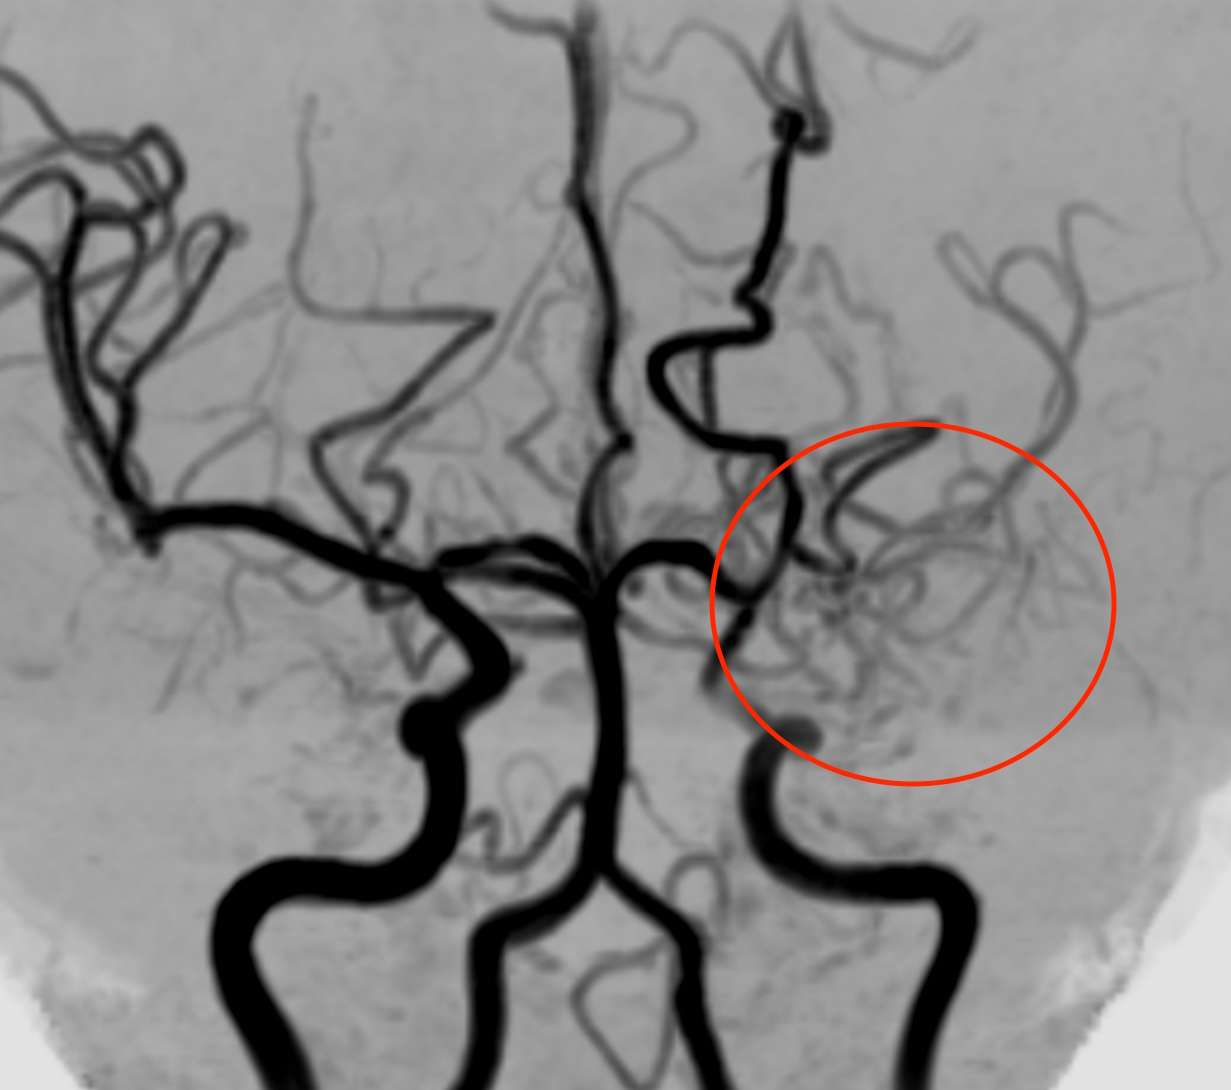

※下は他のもやもや病と片頭痛のある方の画像で、左側の内頚動脈が詰まっています。

血管が詰まり血流が悪くなると、それを補おうとして毛細血管が発達してきます。そして、その状態がもやもやと見えるため、「もやもや病」と名付けられました。若い方の脳梗塞や脳出血の原因となります。遺伝子が特定されていますが、必ずしも全員が発病するわけではありません。